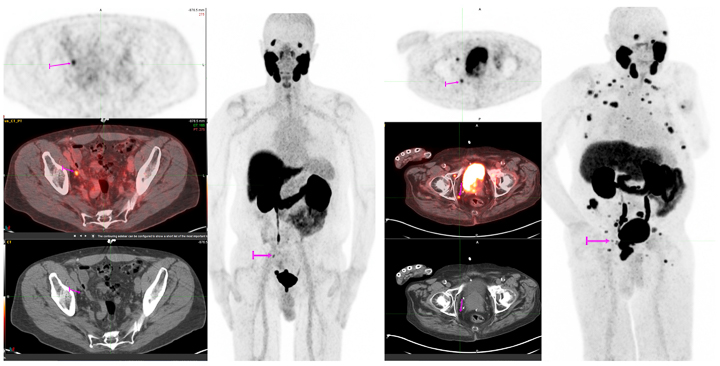

Our Nuclear Medicine and Cancer and Molecular Imaging Divisions are excited to announce the roll-out of our newest PET tracer, 18F-PSMA for prostate cancer PET/CT imaging with Shields Health Care Group. This new tracer is addressing an umet need in prostate cancer care and can detect substantially more prostate cancer lesions compared to conventional imaging. These high-quality exams are allowing us to find small sites of disease and providing clinicians with the information they need to make treatment decisions. The figures show examples of how this tracer is able to detect metastatic disease in 4 mm (left) and 6 mm (right) lymph nodes, that would otherwise not meet pathologic size criteria by CT.

Images provided by Lacey McIntosh, DO, MPH, Division Chief Oncologic and Molecular Imaging, Department of Radiology, UMass Chan Medical School.